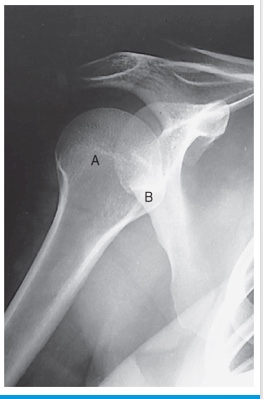

clavicle

A

coracoid process

B

glenoid fossa

C

acromion process

D

lesser tubercle

E

humeral head

F

external rotation

position of humerus?

internal rotation

neutral rotation